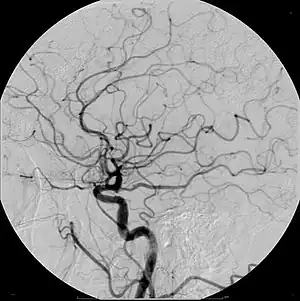

- Angiography (arterial investigations)